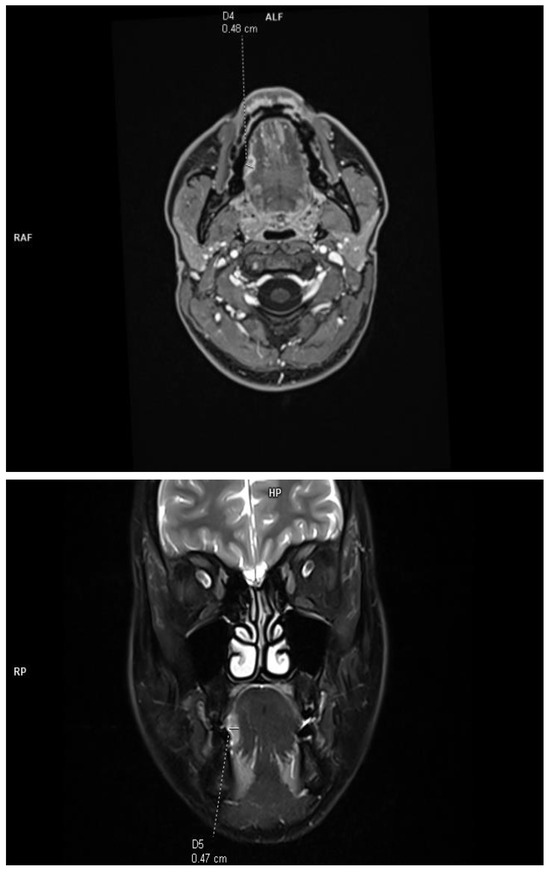

The DOI was measured (in T1-weighted DIXON images and T2-weighted fat-saturated images) from the level of the mucosal surface adjacent to the tumor to the deepest point of invasion in axial or coronal scans, depending on the location of the tumor. The histopathological DOI was measured from the basement membrane of the epithelium using an imaginary line connecting it to the basement membrane of normal squamous cells (Protocol for the Examination of Specimens from Patients with Cancers of the Oral Cavity; version 4.2.0.0). This study excluded deeply ulcerated tumors, where the radiological measurements are much smaller than those of histopathological and exophytic tumors, and the histopathological DOI is 0. This allowed for a reliable assessment of the effectiveness of radiological imaging in relation to histopathological results. Due to the criteria used, the concept of tumor thickness (TT), which, according to the Eighth Edition AJCC manual, is not included in the clinical classification, was deliberately not introduced into this study. The tumor size was assessed in two orthogonal axes according to the Eighth Edition AJCC classification. All tumors assessed in this study were soft tissues (tongue and floor of the mouth), and no bone infiltration was assessed (Figure 1).

Figure 1.

Example of DOI measurements performed in T1-weighted axial plane and T2-weighted coronal plane.